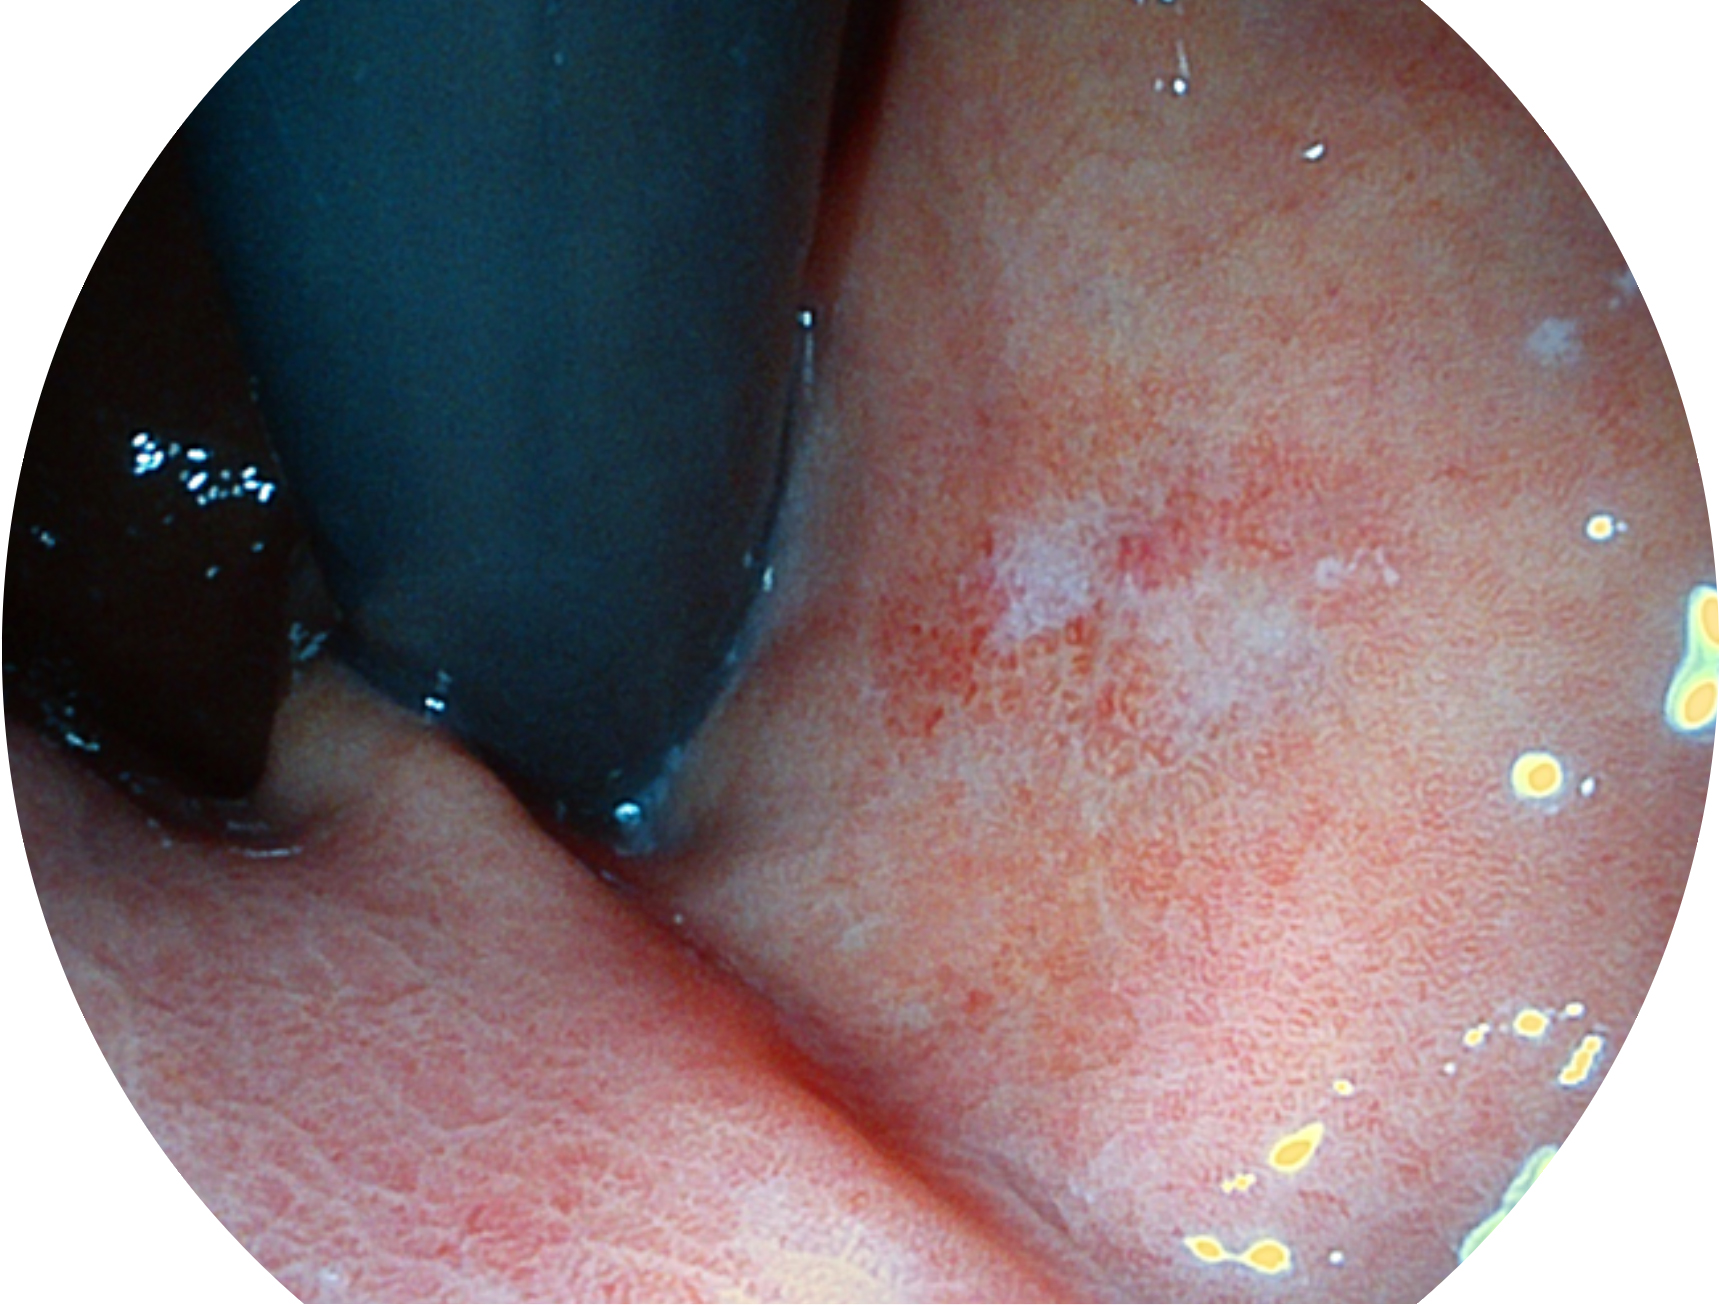

诸侯快讯官网新开发的内镜染色技术,主要是基于多波长LED 光源的开发,VLS-55Q 四波长LED 光源是由四个不同颜色的LED光按照相应照明模式所规定的特定发光比例进行合束后形成,合束后形成的照明光的光谱由红光、绿光、蓝光及蓝紫光这四个不同的波段范围构成。具有更高光谱自由度,通过光谱比例的控制,实现了聚谱成像技术,英文全称为“Spectral Focused Imaging, SFI”,缩写为“SFI”和光电复合染色成像技术,英文全称为“Versatile Intelligent Staining Technology, VIST”,缩写为“VIST”。